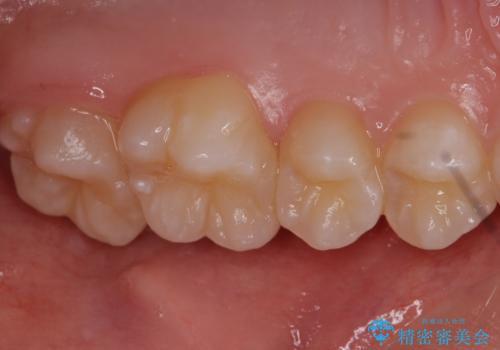

他院で治療した部分の気泡 セラミックインレーでの修復

- 左上6 セラミックインレー 77,000円費用は治療当時の料金となります

気泡が入ってしまっている部位は歯ブラシでのお掃除が難しく、放置してしまうと虫歯が広がってしまうリスクもあるため精度の良い詰め物で修復処置を行います。